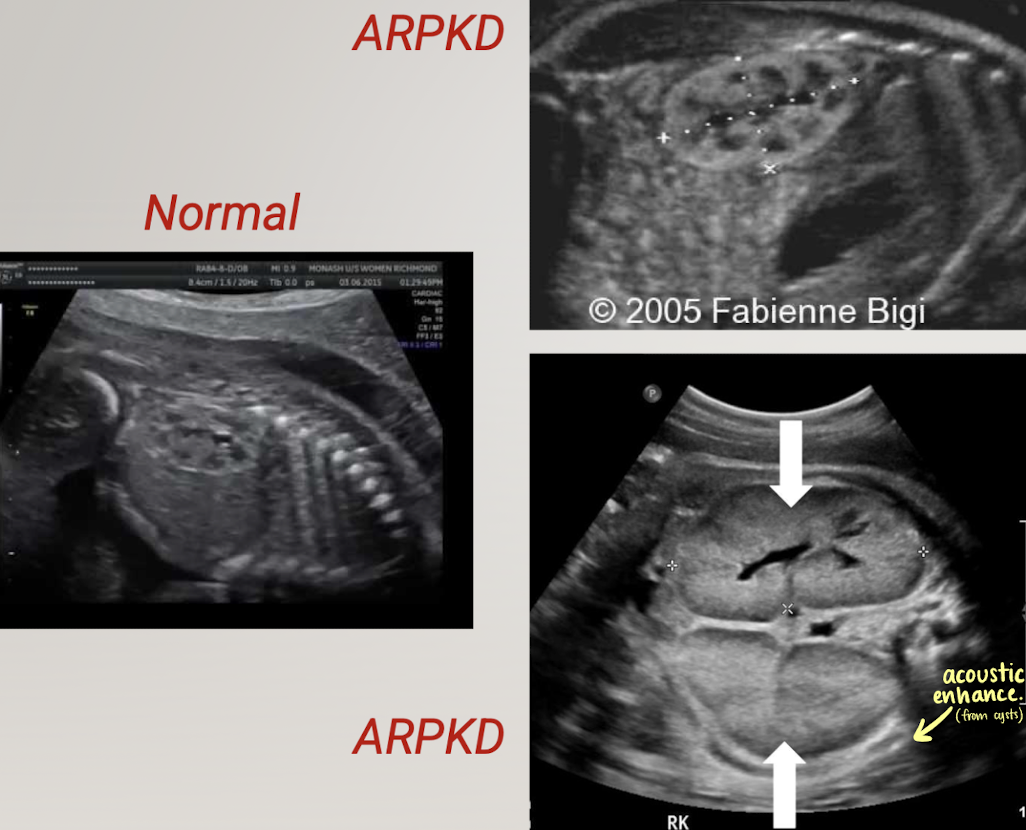

what is the pathology?

ARPKD (autosomal recessive polycystic kidney disease)